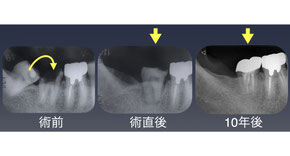

「左下の歯が痛い」

左下第一大臼歯を抜歯し上顎の親知らずを移植した。